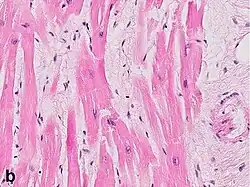

Under the microscope, myocardial infarction presents as a circumscribed area of ischemic, coagulative necrosis (cell death). On gross examination, the infarct is not identifiable within the first 12 hours.[20]

Although earlier changes can be discerned using electron microscopy, one of the earliest changes under a normal microscope are so-called wavy fibers.[21] Subsequently, the myocyte cytoplasm becomes more eosinophilic (pink) and the cells lose their transversal striations, with typical changes and eventually loss of the cell nucleus.[22] The interstitium at the margin of the infarcted area is initially infiltrated with neutrophils, then with lymphocytes and macrophages, who phagocytose ("eat") the myocyte debris. The necrotic area is surrounded and progressively invaded by granulation tissue, which will replace the infarct with a fibrous (collagenous) scar (which are typical steps in wound healing). The interstitial space (the space between cells outside of blood vessels) may be infiltrated with red blood cells.[20]

These features can be recognized in cases where the perfusion was not restored; reperfused infarcts can have other hallmarks, such as contraction band necrosis.[23]